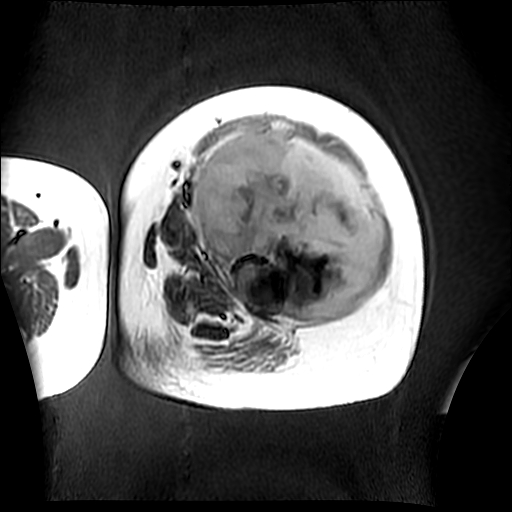

左侧大腿外伤10余年,当时情况不清,发现左侧大腿肿胀7年余,而后又有多次外伤史,近1年来出现疼痛,减重半年。查体:左侧大腿肿胀明显,皮温、肤色正常。

增强

软组织肿块,股骨破坏,增强不均匀强化-----支持恶性肿瘤